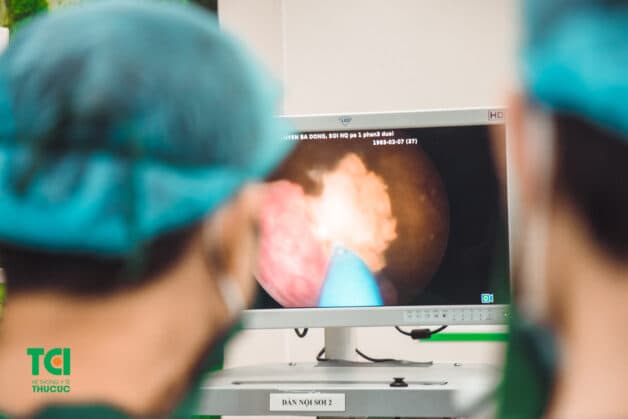

Dưới gây mê toàn thân hoặc gây tê ngoài màng cứng, ống soi niệu quản được đưa qua niệu đạo, vào bàng quang và lên niệu quản. Nhờ hệ thống camera, ống soi niệu quản cho phép quan sát rõ lòng niệu quản và đài bể thận hỗ trợ chẩn đoán chính xác các bệnh lý. Hơn thế nữa, qua ống soi ta có thể đưa vào niệu quản các dụng cụ đặc biệt để tán sỏi, gắp sỏi, lưỡi dao nội soi để rạch niệu quản hay cắt mảnh bệnh phẩm. Và cuối cùng là cho phép đặt một ống thông đặc biệt 2 đầu có hình chữ J (sonde JJ) nằm từ bể thận qua niệu quản xuống bàng quang. Ống thông này cho phép nước tiểu chảy từ thận xuống bàng quang, tránh hiện tượng tắc hoặc hẹp lòng niệu quản. Ống JJ không gây phiền phức gì cho bệnh nhân và thường được rút ra một cách dễ dàng qua soi bàng quang.

Ống nội soi niệu quản có 3 loại: cứng, nửa cứng và mềm. Ống soi mềm chủ yếu dùng cho chẩn đoán, đặc biệt nó cho phép quan sát tới tận đài thận giữa và dưới. Loại ống soi cứng và nửa cứng ngoài tác dụng chẩn đoán, chủ yếu dùng để điều trị.